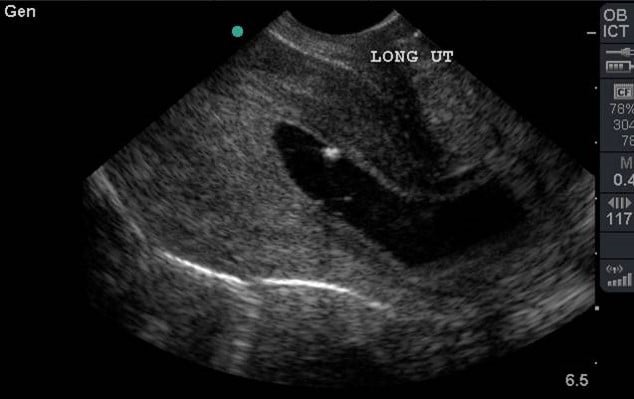

- A Fetal Pole develops weeks 6-7 and a heart rate is visible in the same time frame (Illustration 9, Video 9)

- Fetal heart rate is best by placing an M-Mode spike across the flickering fetal heart and measuring the repeating pattern. (Illustration 9)

- Do not use pulse wave Doppler as it focuses too much energy (heat) on the fetus and goes against the ALARA (as low as reasonably achievable) principle.